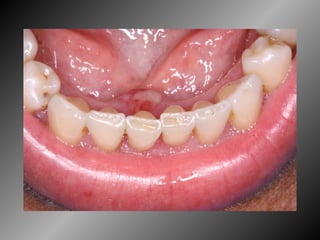

Granuloma Piogênico Lesão Nodular Séssil ou pediculada Avermelhada ou vinhosa Sangramento espontâneo e áreas de micro-ulceração superficial

Granuloma Piogênico Lesões nodulares de coloração avermelhada ou vinhosa Provavelmente uma reação inflamatória exagerada ao trauma menor Crescimento rápido, às vezes sangramento espontâneo Ocorre em qualquer idade mas parece mais freqüente em adultos jovens e adolescentes  Localização mais comum: gengiva (NEVILLE,2001)

Granuloma Piogênico Lesões mais antigas, são menos vasculares e mais fibrosas Papila interdental e regiões anteriores são áreas preferenciais, principalmente por vestibular (BORK,1996)

Granuloma Piogênico LesãoNodular Séssil ou pediculada Avermelhada ou vinhosa Sangramento espontâneo e áreas de micro-ulceração superficial

Granuloma Piogênico Lesõesnodulares de coloração avermelhada ou vinhosa Provavelmente uma reação inflamatória exagerada ao trauma menor Crescimento rápido, às vezes sangramento espontâneo Ocorre em qualquer idade mas parece mais freqüente em adultos jovens e adolescentes Localização mais comum: gengiva (NEVILLE,2001)

Granuloma Piogênico Lesõesmais antigas, são menos vasculares e mais fibrosas Papila interdental e regiões anteriores são áreas preferenciais, principalmente por vestibular (BORK,1996)